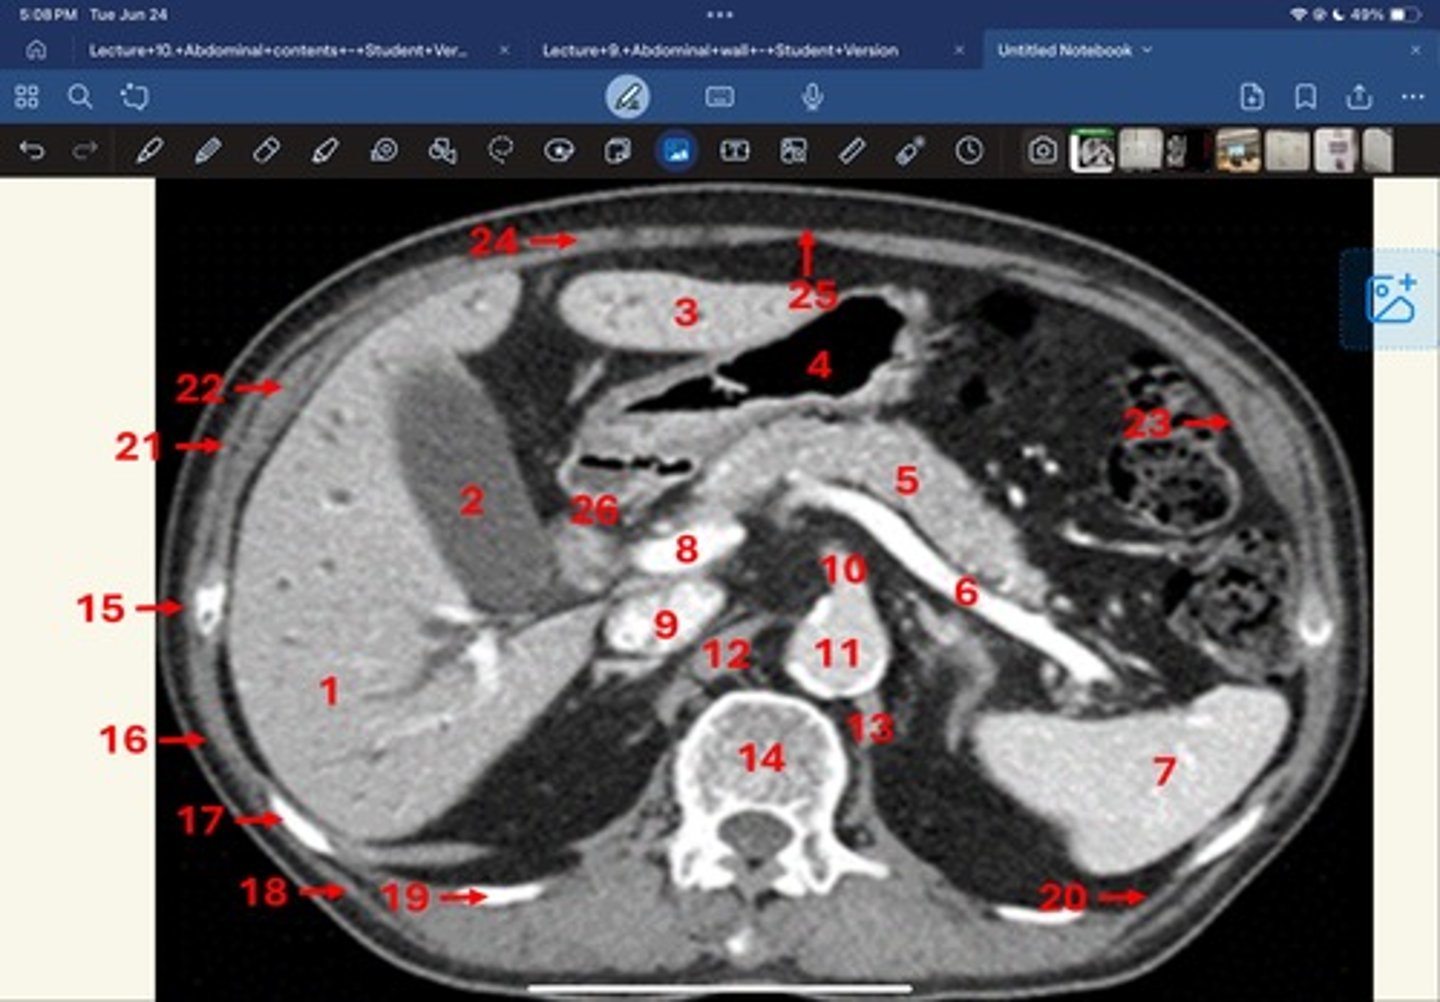

Right lobe of liver

What is 1

Gallbladder

What is 2

Left lobe of liver

What is 3

Stomach, pylorus

What is 4

Pancreas

What's 5

Splenic vein

What's 6

Spleen

What's 7

superior mesenteric vein

What's 8

Inferior vena cava

What's 9